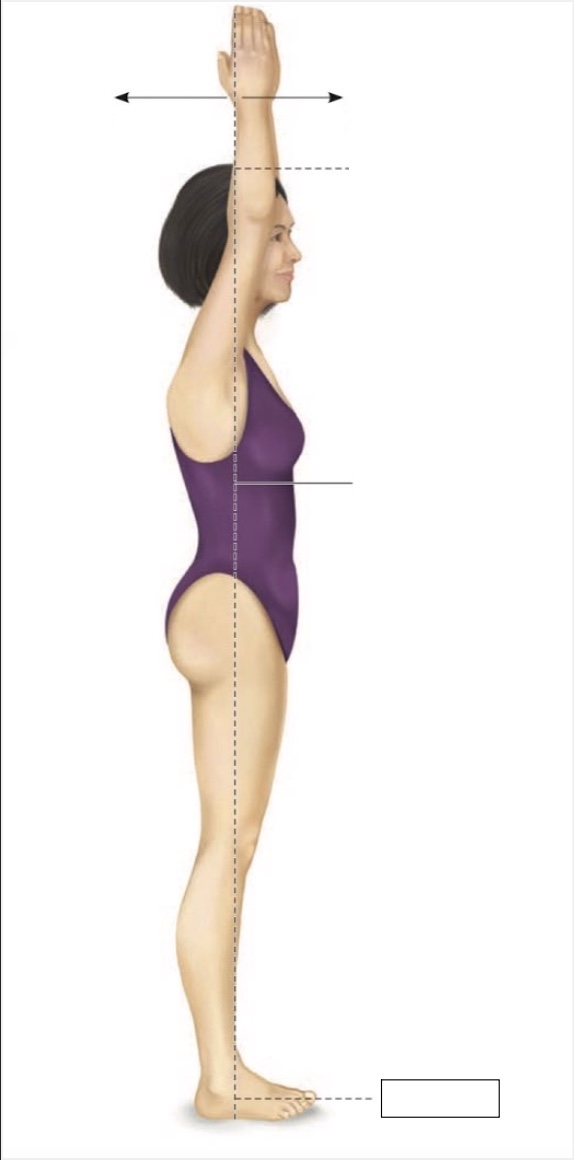

Superior

Inferior

Midline

Proximal

Distal

Medial

Lateral